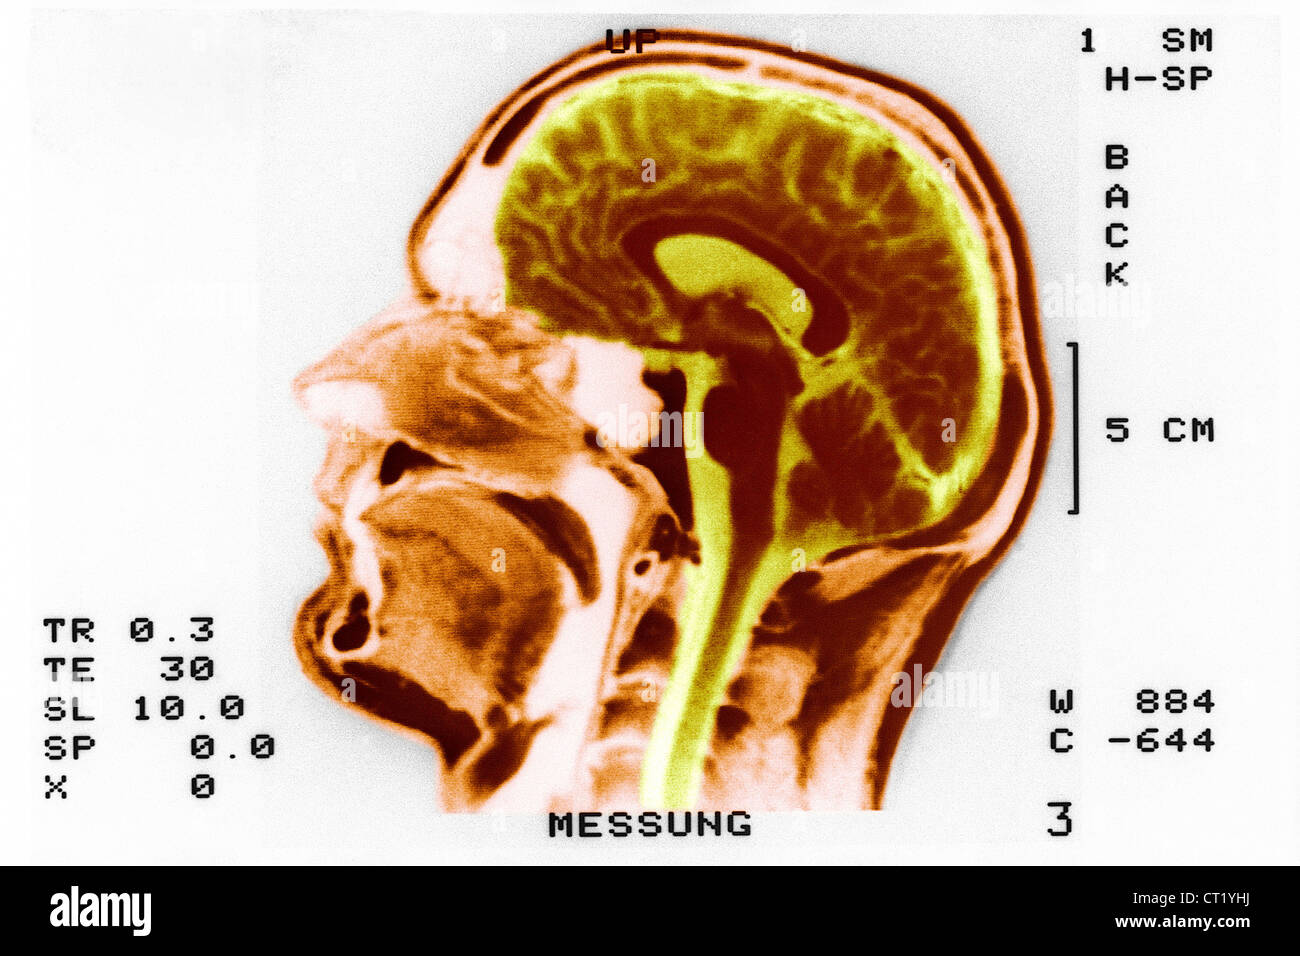

From www.alamy.com

MRI brain scan Sagittal and coronal view with reference line for detect How Do I Know If I Need A Brain Scan Major structural changes, such as pressure from a tumor pushing on one side of the brain can be detected with a brain ct scan. How to cope with the mri experience. a brain ct scan visualizes the structure of the brain and skull, and it can identify blood in and around the brain. Brain damage, a stroke or A. How Do I Know If I Need A Brain Scan.